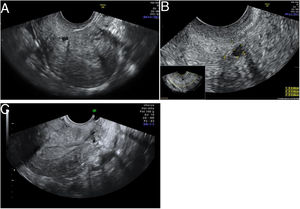

DiscusiónDiagnóstico del istmoceleEl istmocele se define como una indentación ≥2mm en el miometrio sobre la cicatriz de una cesárea anterior. Se ha descrito el uso de distintas pruebas de imagen para su diagnóstico, con diferentes ventajas e inconvenientes (tabla 1). Aunque no existen criterios diagnósticos definitivos, recientemente se realizó un consenso con un grupo de expertos en el que se establecieron criterios para estandarizar la medición del istmocele en mujeres no gestantes mediante ecografía transvaginal (Delphi Ultrasonographic Niche Evaluation)5. Para ello se deben tomar tres medidas básicas: longitud y profundidad en el plano sagital uterino (medio o lateral), y grosor de la lesión en un plano transverso (fig. 2)5. Además, se debe valorar si existe ramificación y su complejidad, clasificando así los istmoceles en tres tipos (fig. 3). Aparte de estas medidas, es fundamental medir el grosor del miometrio residual (GMR) desde la base y la rama más cercana a la serosa. El GMR será la medición más importante, ya que, en caso de tratamiento, el tipo de abordaje quirúrgico dependerá de este grosor residual.

Mediciones básicas de un istmocele: longitud y profundidad se deben tomar en un plano sagital, y el grosor en un plano transverso. Imagen adaptada de Jordans et al.5.